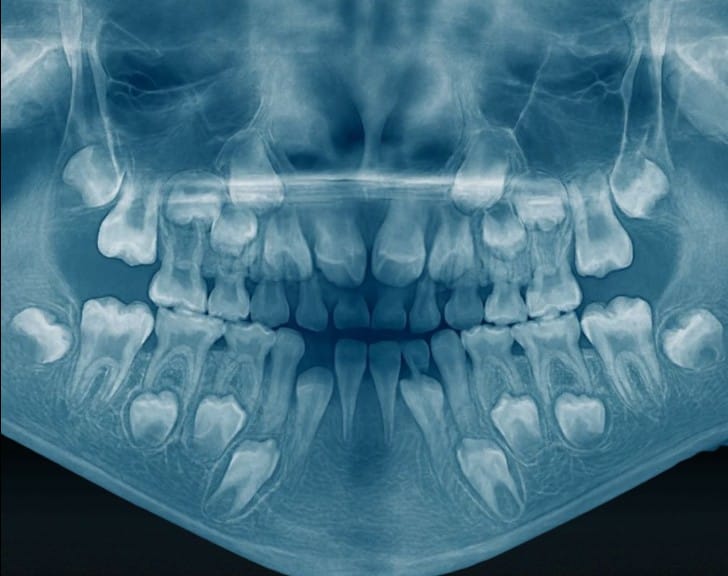

Răng sữa qua phim xquang

Răng vĩnh viễn đã hình thành từ rất sớm

Ngay từ những năm đầu đời, bên trong xương hàm của trẻ, mầm răng vĩnh viễn đã bắt đầu phát triển.

Men răng đang được hình thành.

Hình thể thân răng đang được tạo dựng.

Cấu trúc răng được xây dựng từng lớp một.

Khi một răng sữa bị sâu tiến triển đến tủy, tình trạng nhiễm trùng không chỉ khu trú tại răng đó. Chóp chân răng sữa nằm rất gần mầm răng vĩnh viễn. Vi khuẩn và các sản phẩm viêm có thể làm gián đoạn quá trình hình thành men và phát triển thân răng vĩnh viễn.